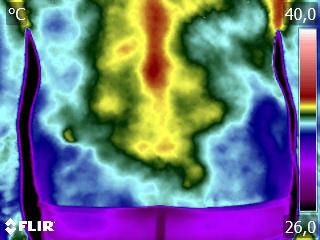

Como no caso do termograma abaixo de uma paciente do sexo feminino, 48 anos, sem comorbidades e que sofreu uma entorse de tornozelo há mais de uma semana e, mesmo tendo passado pela emergência com exame de Raio X, não foi atestado lesões graves e nem fraturas. Foi realizado uma Análise Termofuncional e detectado alterações térmicas condizentes com o relato de dor.

Estas informações foram suficientes para solicitação de exame de imagem (ressonância magnética) que atestou microfratura e outras lesões decorrentes do trauma.